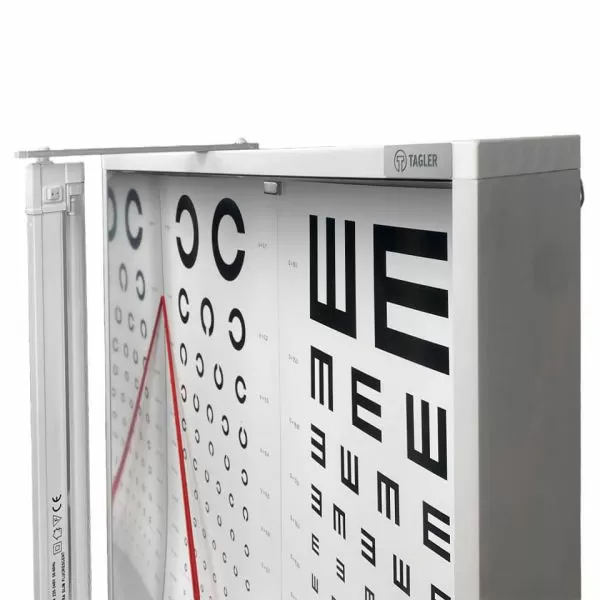

Арт.: Ш4 FS1

4 830 руб./шт

Арт.: 9001LED

8 835 руб./шт